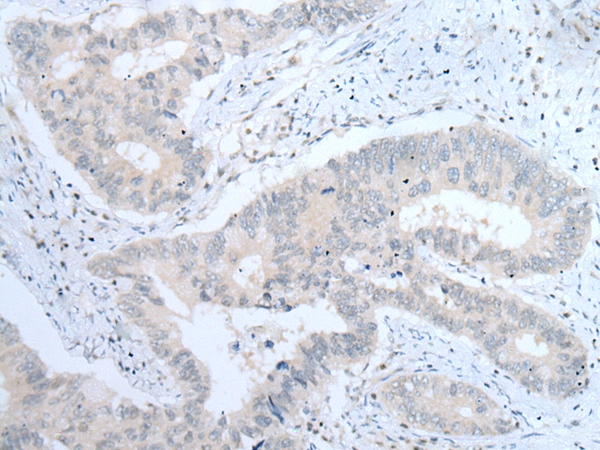

IHC positive control:

Human colorectal cancer

IHC Recommend dilution:

25-100